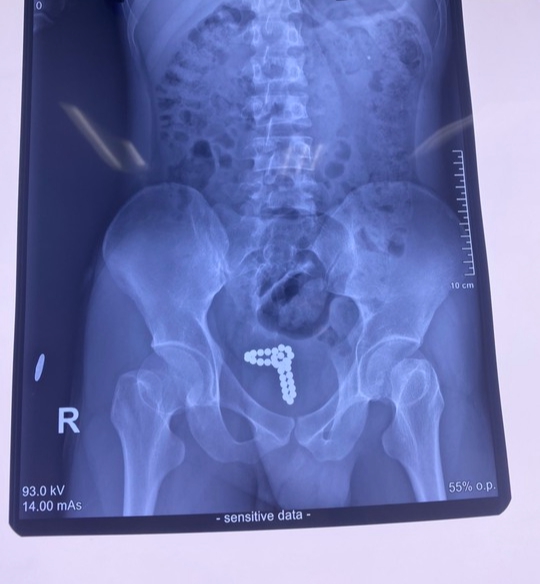

01/03/2023 20:5030 viên bi kim loại mắc kẹt trong 'cậu nhỏ' của thanh niên 22 tuổi

Ngày 1/3, thông tin từ Bệnh viện Nhân Dân 115 cho biết, tại đây vừa tiếp nhận và can thiệp cho một trường hợp bị dị vật niệu đạo rất hy hữu. Bệnh nhân là nam thanh niên N.B.T (22 tuổi, ngụ tại TPHCM) nhập viện cấp cứu trong tình trạng tiểu ra máu.

Trước đó, nam thanh niên đã dùng chuỗi bi kim loại nhét vào bộ phận sinh dục để “tự sướng”. Trong lúc cao trào khoái cảm thì chuỗi bi kim loại bất ngờ tuột vào niệu đạo không thể tự lấy ra khiến bệnh nhân đi tiểu ra máu phải nhập viện cấp cứu.

Tại Đơn vị Nam khoa, qua thăm khám lâm sàng và làm các xét nghiệm, chụp X-quang bụng, các bác sĩ xác định dị vật là chuỗi hạt kim loại có từ tính dính với nhau thành chuỗi đang nằm trong bàng quang của người bệnh. Dị vật gây tổn thương bàng quang là nguyên nhân khiến bệnh nhân tiểu ra máu.

Sau hội chẩn, các bác sĩ đã tiến hành phẫu thuật mở bàng quang để gắp dị vật. Qua các thao tác chuyên môn theo vết mổ khoảng 2cm, các bác sĩ đã lấy ra 30 viên bi kim loại nhiều màu sắc, mỗi viên có kích thước khoảng 5mm dính với nhau thành chuỗi. Sau phẫu thuật, tình trạng sức khỏe của bệnh nhân đã ổn định.